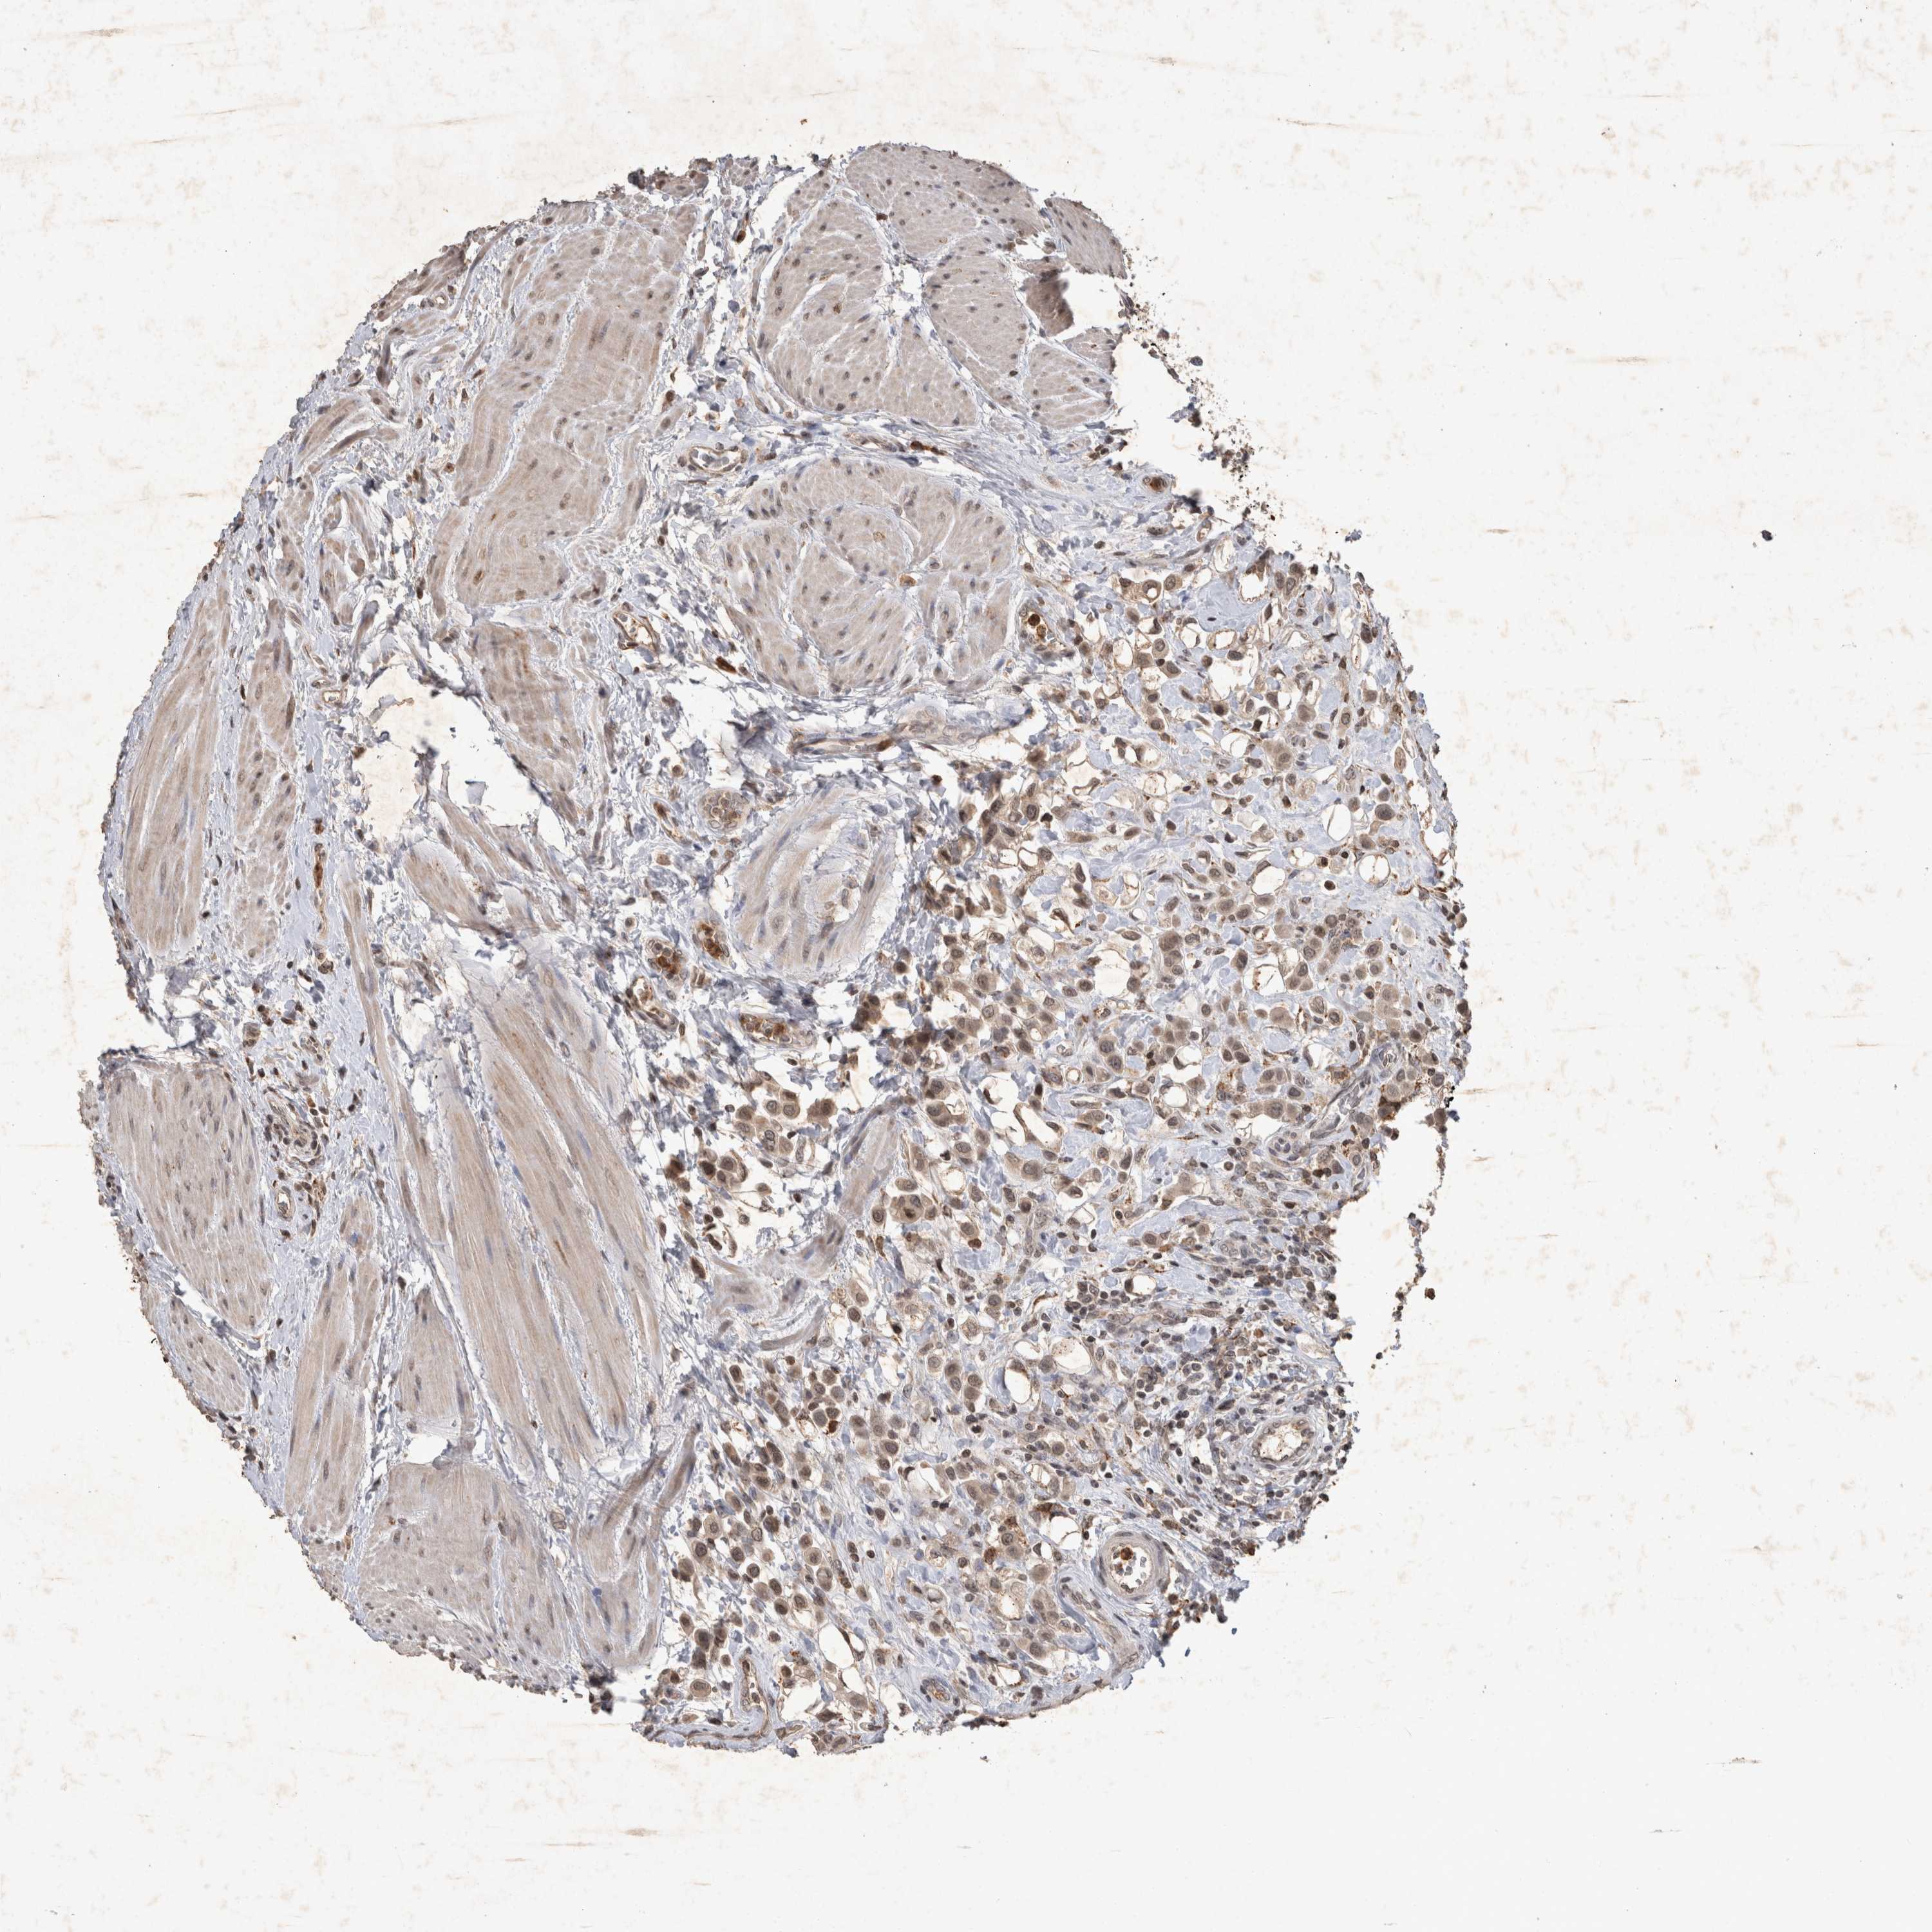

UROTHELIAL CANCER - Protein expressioni

A mouse-over function shows sample information and annotation data. Click on an image to view it in a full screen mode. Samples can be filtered based on level of antibody staining by selecting one or several of the following categories: high, medium, low and not detected. The assay and annotation is described here.

Note that samples used for immunohistochemistry by the Human Protein Atlas do not correspond to samples in the TCGA dataset.

Antibody stainingi

Antibody staining in the annotated cell types in the current human tissue is reported as not detected, low, medium, or high, based on conventional immunohistochemistry profiling in selected tissues. This score is based on the combination of the staining intensity and fraction of stained cells.

Each image is clickable and will lead to virtual microscopy that enables deeper exploration of all samples and also displays staining intensity scores, fraction scores and subcellular localization as well as patient and tissue information for each sample.

Antibody CAB025973

Staining

High

Medium

Low

Not detected

Intensity

Strong

Moderate

Weak

Negative

Quantity

>75%

75%-25%

<25%

None

Location

Nuclear

Cytoplasmic/membranous

Cytoplasmic/membranous,nuclear

Urothelial carcinoma, Low grade

Urothelial carcinoma, High grade